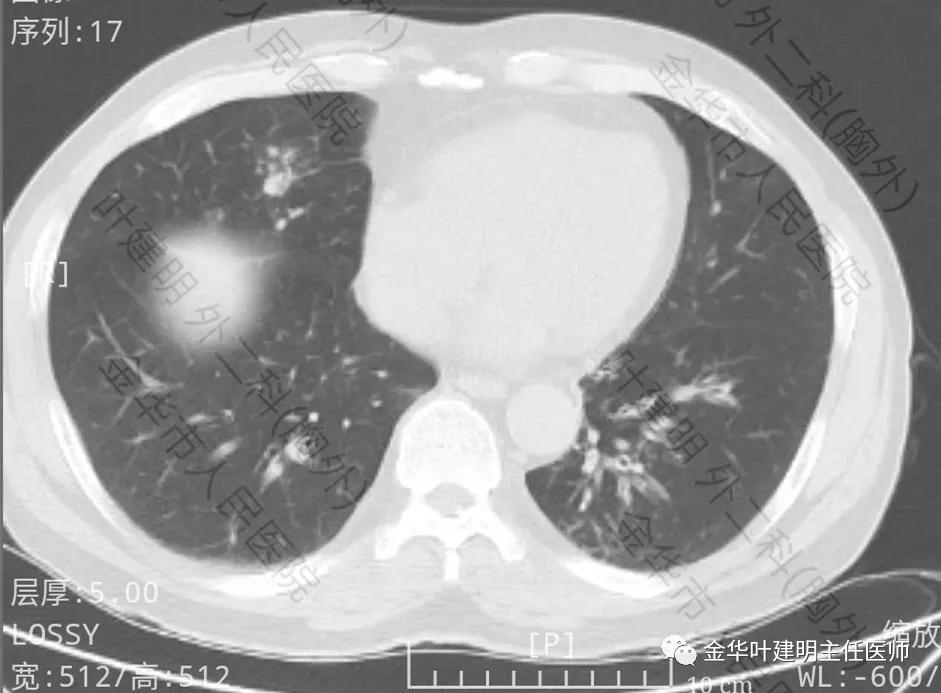

上图示右中叶及左下叶感染灶